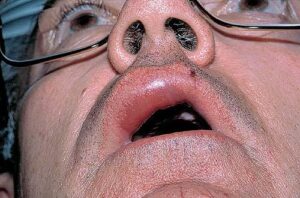

Angioedema is the swelling of deep dermis, subcutaneous or submucosal tissue due to vascular leakage.1 It was first described in 1586.2 Other terms, such as giant urticaria,3 Quincke edema,4 and angioneurotic edema,5 have also been used in the past to describe this condition. Clinically, angioedema is usually nonpitting and nonpruritic. The area of involvement is often skin-colored or slightly erythematous. Depending on the area of swelling, pain can be absent or mild, as in most peripheral or facial swelling, or can be very severe, as in gastrointestinal angioedema. Laryngeal swelling is life-threatening. It should be treated as a medical emergency.

Patients usually describe swelling of the face (eg, eyelids, lips), tongue, hands, and feet. It can be acute or chronic, and each episode of angioedema may last a few hours to a few days. A local burning sensation and pain can be observed without pronounced itchiness or local erythema. Abdominal pain can sometimes be the only presenting symptom of angioedema. Throat tightness, voice changes, and trouble breathing may indicate airway involvement.

For skin involvement, examination can easily identify areas of swelling with or without erythematous skin, often with ill-defined margins. Some cases of angioedema occur in patients with urticaria.

Uvula or tongue swelling can be visualized directly (see image below). However, a laryngoscopy is needed to assess laryngeal or vocal cord involvement.